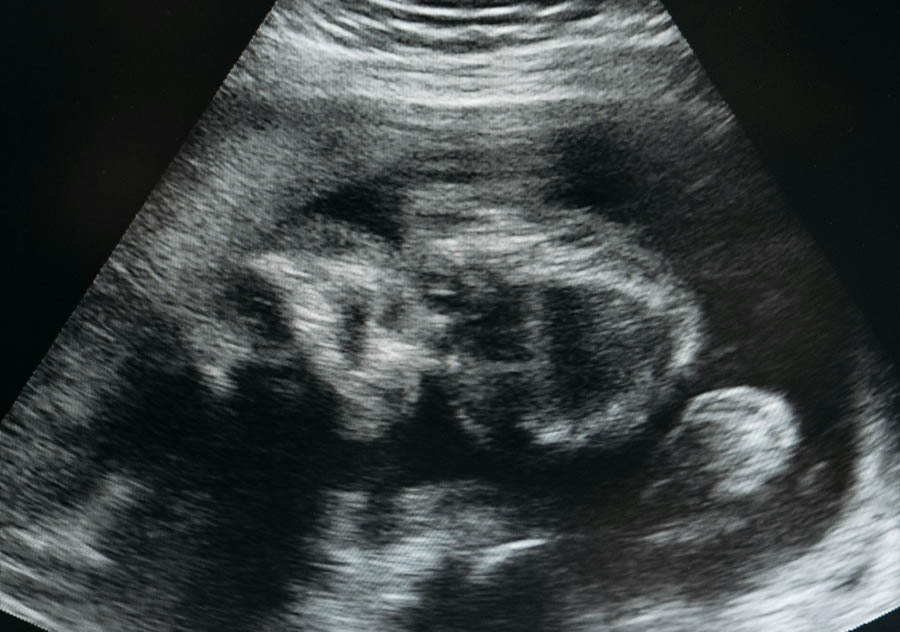

Ultrasound plays a pivotal role in the hotly debated world of abortion. As of September 2023, 27 states regulate the provision of an ultrasound by an abortion provider. Of these 27 states, 10 mandate an abortion provider perform an ultrasound at the time of an abortion and eight states require that the provider of an abortion offer the patient the opportunity to view the ultrasound image prior to an abortion.

The authors studied and reviewed the electronic medical records of over 15,000 women seeking abortion at 19 different Planned Parenthood facilities in the city of Los Angeles during the 2011 calendar year. The goal of the study was to “see if a woman’s decision to view or not view her ultrasound image was associated with a decision to continue the pregnancy.”

A little over one-half of the total group of women underwent an abortion without having an ultrasound performed. This group of 8,718 women was compared to the remaining 6,450 women who opted to voluntarily view their fetus by ultrasound prior to deciding on whether to continue with the abortion.

In this study, the authors reported 99% of those women who presented to Planned Parenthood and who did not view an ultrasonographic image of their embryo, terminated their pregnancy. Of those who presented to Planned Parenthood for an intended abortion, 98.4% of the 6,450 women who chose to view the ultrasound image of the life within their uterus proceeded with an abortion.

The abortion advocates don’t want to admit nor even mention what’s buried deep in the article – that “women at 17-19 weeks of gestation…were almost 20 times as likely to continue the pregnancy compared with women at less than 9 weeks of gestation” after seeing their baby on ultrasound.

To their credit however, the authors did point out the linear relationship between gestational age at the time of viewing an ultrasound image and the decision not to proceed with their planned abortion.

In other words, the further along a woman is at the time of viewing her baby by ultrasound, the more likely she is to continue her pregnancy and not proceed with an abortion. The presumption being, of course, that the woman realized the kicking she had just visualized on the ultrasound actually did represent life.

Wherever the truth resides, the indisputable fact is the performance of an ultrasound can have a profound impact on a pregnant woman considering an abortion and whether she chooses life rather than an abortion; the incidence of abortion can only be lowered.